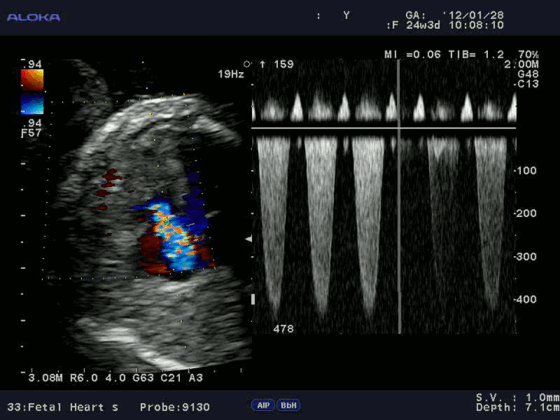

Цветовой допплер (Color Doppler). Цветовой допплер - аналог импульсного допплера, где направление и скорость кровотока картируется различным цветом. Так кровоток к датчику принято картировать красным цветом, от датчика - синим цветом. Турбулентный кровоток картируется сине-зелено-желтым цветом.

Допплерэхокардиография позволяет измерить все вышеперечисленные параметры, которые очень важны при оценке детской сердечной патологии (врожденные пороки) без использования инвазивной процедуры — катетеризации сердца. Помимо этого, назначение эхокардиографии с допплеровским анализом ребенку не несет никакой угрозы по сравнению с компьютерной томографией, где используется рентгеновское излучение.